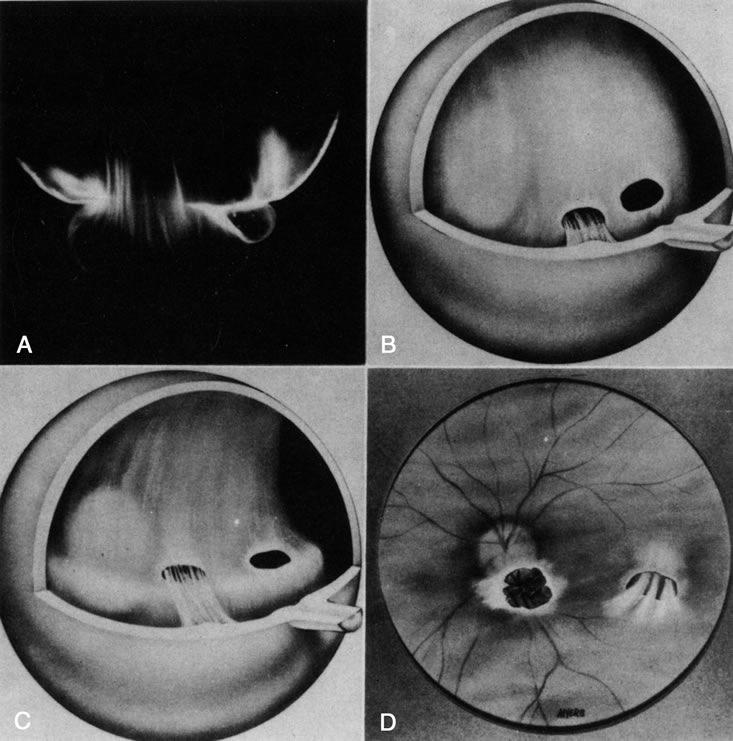

Persistent hyperplastic primary vitreous (PHPV) was first described by Reese28 as a congenital malformation of the anterior portion of the primary vitreous appearing as a plaque of retrolental fibrovascular connective tissue. This tissue is adherent to the posterior lens capsule and extends laterally to attach to the ciliary processes, which are elongated and displaced centrally. Although 90% of cases are unilateral, many of the fellow eyes have Mittendorf's dot or other anomaly of anterior vitreous development.29 A persistent hyaloid artery, often still perfused with blood, arises from the posterior aspect of the retrolental plaque in the affected eye. In severe forms, there is microphthalmos with anterior displacement of the lens-iris diaphragm, shallowing of the anterior chamber, and secondary glaucoma. PHPV is believed to arise from abnormal regression and hyperplasia of the primary vitreous.28 Experimental data suggest that the abnormality begins at the 17-mm stage of embryonic development.30 The hyperplastic features result from generalized hyperplasia of retinal astrocytes and a separate component of glial hyperplasia arising from the optic nerve head.31 The fibrous component of the PHPV membrane is presumably synthesized by these astrocytes and glial cells.32 A recent case report with clinicopathologic correlation found that collagen fibrils in this fibrous tissue had diameters of 40 to 50 nm with a cross-striation periodicity of 65 nm. The investigators concluded that the collagen fibrils differed from those of the primary vitreous and suggested that they arose either from a different population of cells or were the result of abnormal metabolism by the same cells that synthesize vitreous collagen.33

The retina is usually not involved in anterior PHPV. Indeed, previous studies have suggested that the anterior form is due to a primary defect in lens development and that vitreous changes are all secondary.34 This postulate has never been substantiated. There are rare instances of posterior PHPV in which opaque connective tissue arises from Bergmeister's papilla and persistent hyaloid vessels (Fig. 1).32,35 These can cause congenital falciform folds of the retina and, if severe, can cause tentlike retinal folds, leading on rare occasions to tractional and/or rhegmatogenous retinal detachment. Font and investigators36 demonstrated the presence of adipose tissue, smooth muscle, and cartilage within the retrolental plaque and suggested that PHPV arises from metaplasia of mesenchymal elements in the primary vitreous.